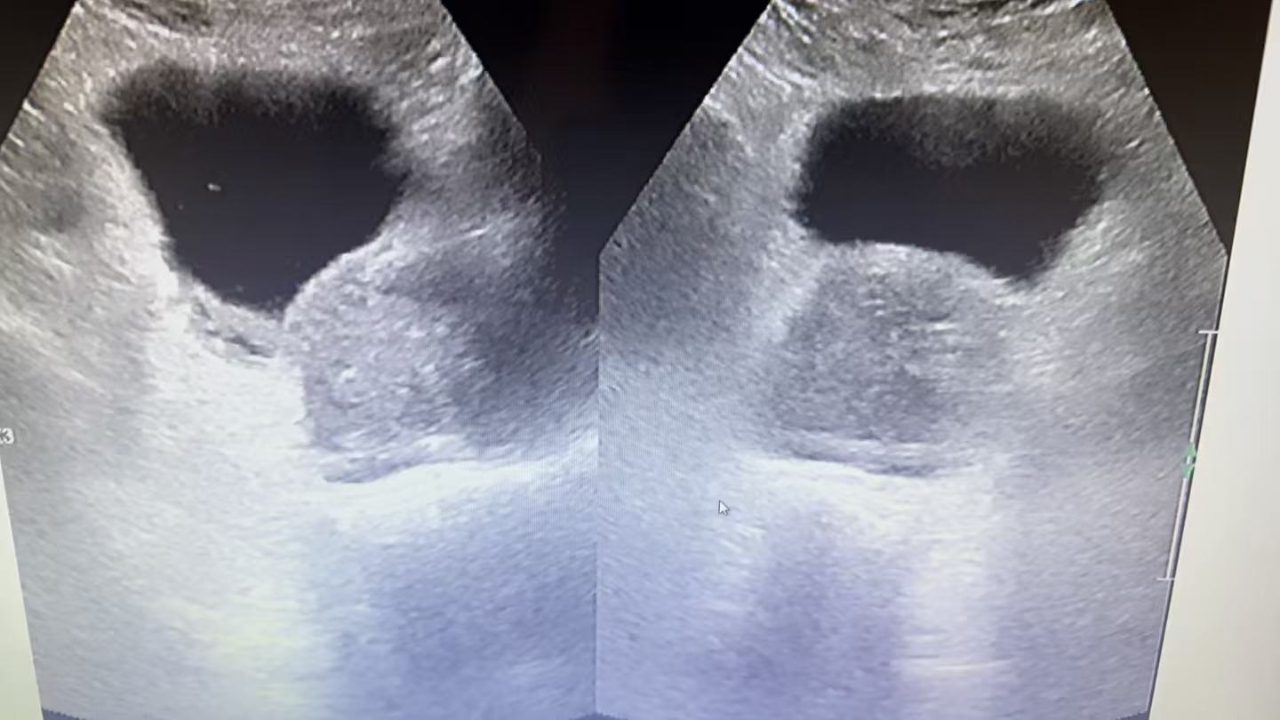

近期 我院普外科连续为两位80多岁高龄的男性患者成功实施了经尿道前列腺电切术。两位患者均因“进行性排尿困难2年,夜尿频(初始每晚7次,渐加重至10次左右)、尿潴留、血尿”反复留置导尿而长期困扰。术前经过麻醉科、心内科等多学科联合评估,精准把控手术指征与风险,确认患者虽然高龄,但手术耐受性良好。 通过内镜微创手术操作,精准切除增生腺体,迅速解除了尿道梗阻。在现代麻醉与微创外科技术的支持下,高龄本身不再是手术的绝对禁区。关键在于由专业团队进行系统、审慎的围手术期评估与管理。 患者安返病房 老年男性前列腺增生极为常见,严重影响着生活质量,夜尿多休息不好,极易引起心脑血管疾病等并发症。许多患者常因“年纪大了,忍一忍”或“害怕手术”而延误治疗,导致反复尿潴留、泌尿系感染、甚至肾功能损害,以至于失去手术治疗机会。 经尿道前列腺电切术作为成熟微创术式,具有创伤小、恢复快、出血少等优势,能有效改善排尿功能,显著提升晚年生活质量。 希望借此案例,提醒广大中老年朋友。若出现尿线变细、起夜频繁、排尿费力等症状,请尽早到泌尿外科就诊。健康不分年龄,科学评估+积极干预,方能畅享晚年。 普外科 联系电话 0431-76297370 联系地址 公主岭市河南广场阳光医院一楼门诊2号诊室